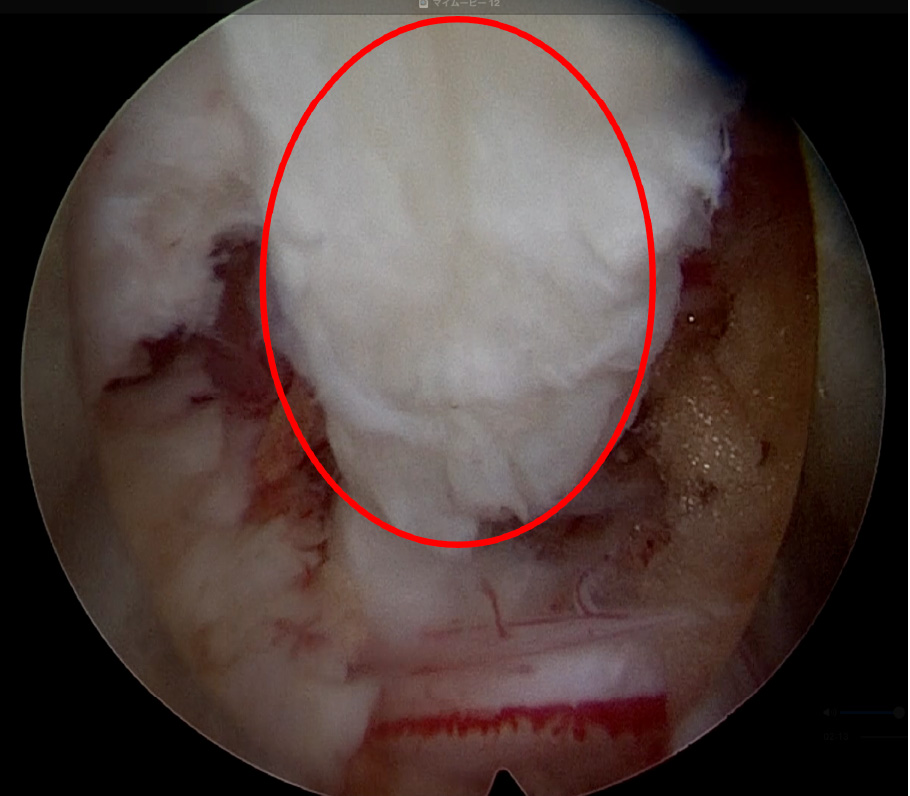

術後:ヘルニアは完全摘出され、神経の圧迫が解除されています。

右図は背中から見た腰椎を示していますが、

少量の骨削除による開窓でヘルニアが摘出されました。